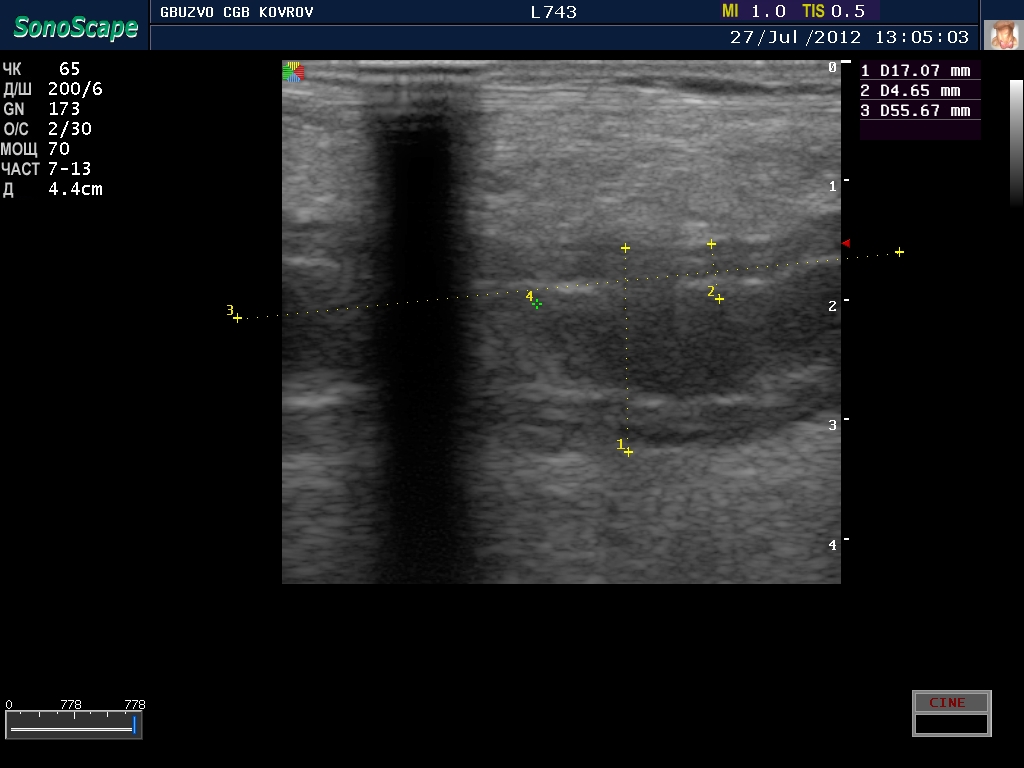

полечили два дня в гастроэнтерологии...состояние ухудшилось, узи контроль----->

Что это такое? Кишка?

ну, скажем так, часть кишечника :D

поподробнее? :shock: бодимаркер находится в правой подвсздошной области, я бы подумал про аппендикс 8-)